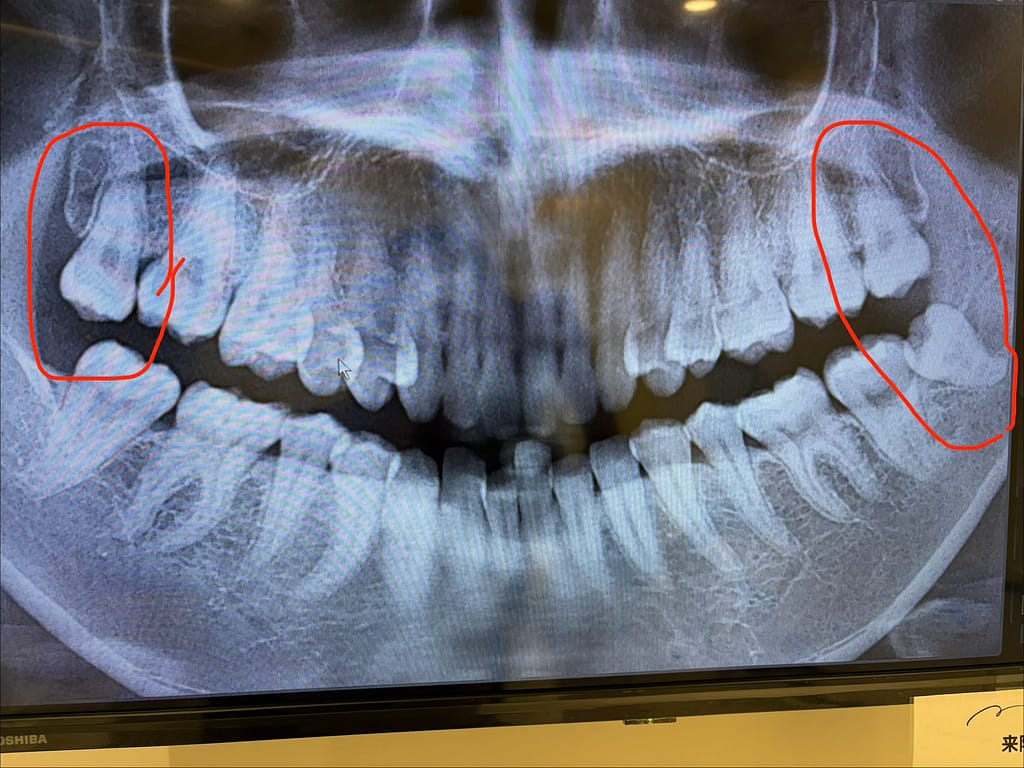

私自身、親知らずを3本抜歯(うち1本は左の下が半埋伏)しました。

半埋伏とは、歯ぐきに一部埋まっている状態の親知らずです。

私の場合は「斜めに生えている半埋伏」だったため、

• 3/13:左上下2本同時に抜歯(下は半埋伏、上はまっすぐ生えている)

特に下の半埋伏の親知らずは、私の場合0.5cm切開してからの、斜めに分割して抜歯しました!

下の半埋伏のためのCT撮影 3,710円